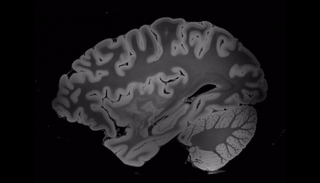

100 ساعة بـ"الرنين المغناطيسي" تكشف أسرار الدماغ

علماء أمريكيون يجرون 100 ساعة كاملة من المسح على الدماغ باستخدام واحدة من أكثر أجهزة التصوير بالرنين المغناطيسي تقدما.